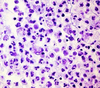

What are the molecular and morphologic changes of the image? ( MDx)

Clinical history and signs: 3 week old puppy, anorexia, dypsnea, abd pain upon palpation, normal rectal temperature

Multifocal, acute renal necrosis and hemorrhage or necrohemorrhagic nephritis

What is the etiology?

Clinical history and signs: 3 week old puppy, anorexia, dypsnea, abd pain upon palpation, normal rectal temperature

Canine herpesvirus-1 (CHV-1)

- red spots are from the virus targeting endothelium

What is the pathogenesis?

Clinical history and signs: 3 week old puppy, anorexia, dypsnea, abd pain upon palpation, normal rectal temperature

Transmission CHV-1 to pup at birth >incubation period of up to 1 week > virus replicates at temperature lower than 37C (98.6F) > endothelial cell tropism > multifocal necrosis in numerous organs